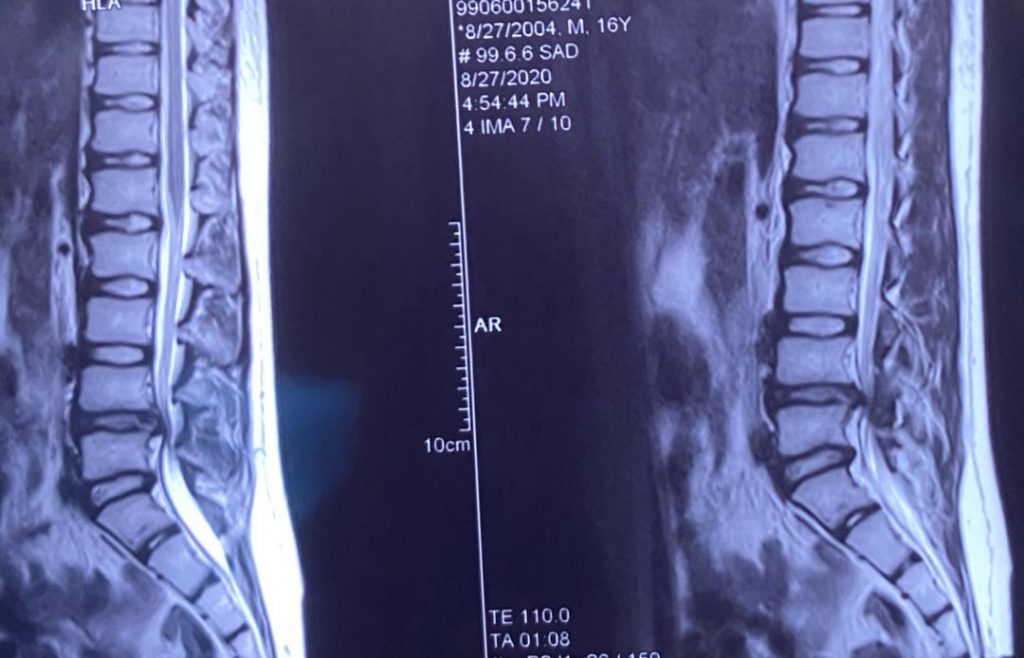

تصاویر قبل ار جراحی

پارگی دیسک و آسیب مفصل فاست L4-L5 وجود داشت که عمل جراحی میکروسکوپیک فنستراسیون و دیسککتومی دوطرفه انجام شد.